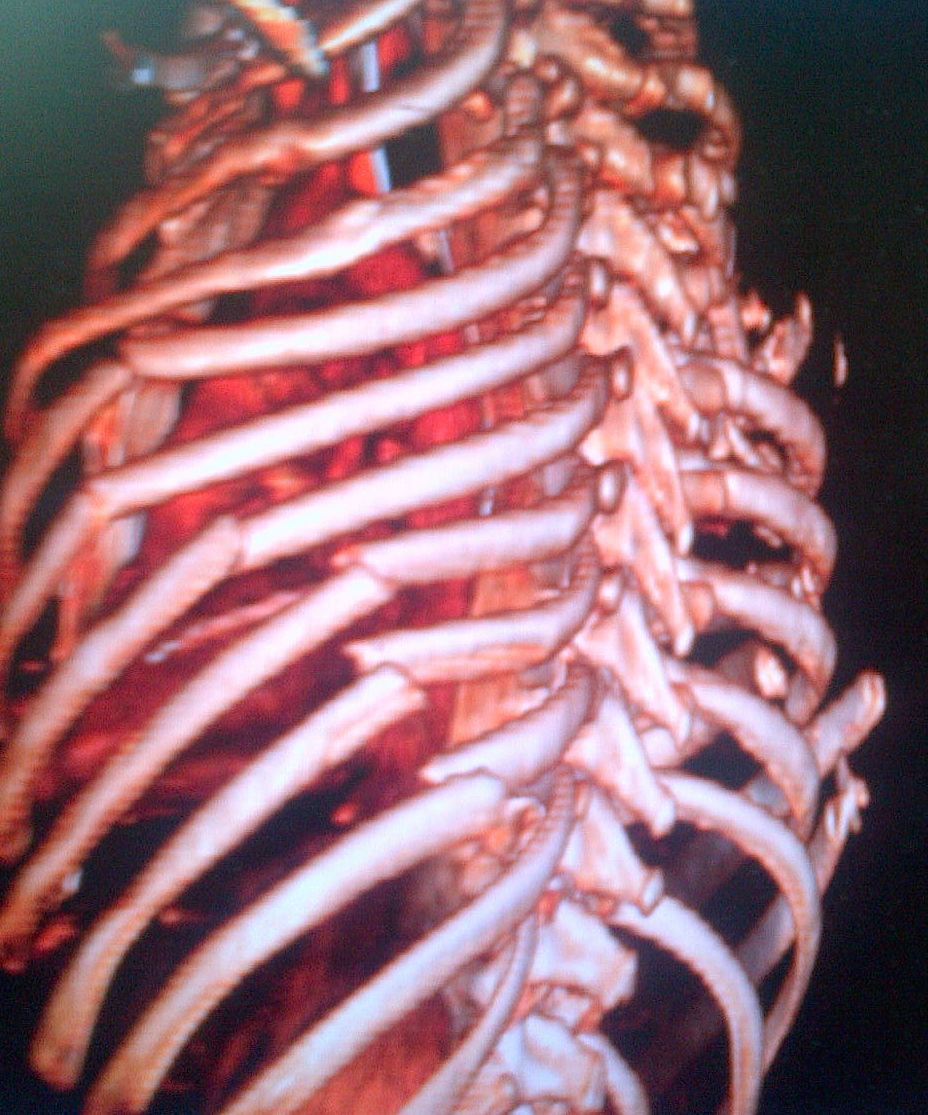

Alters mechanics of ventilation / causes respiratory compromise

- significant morbidity 33%

- significant mortality 12%